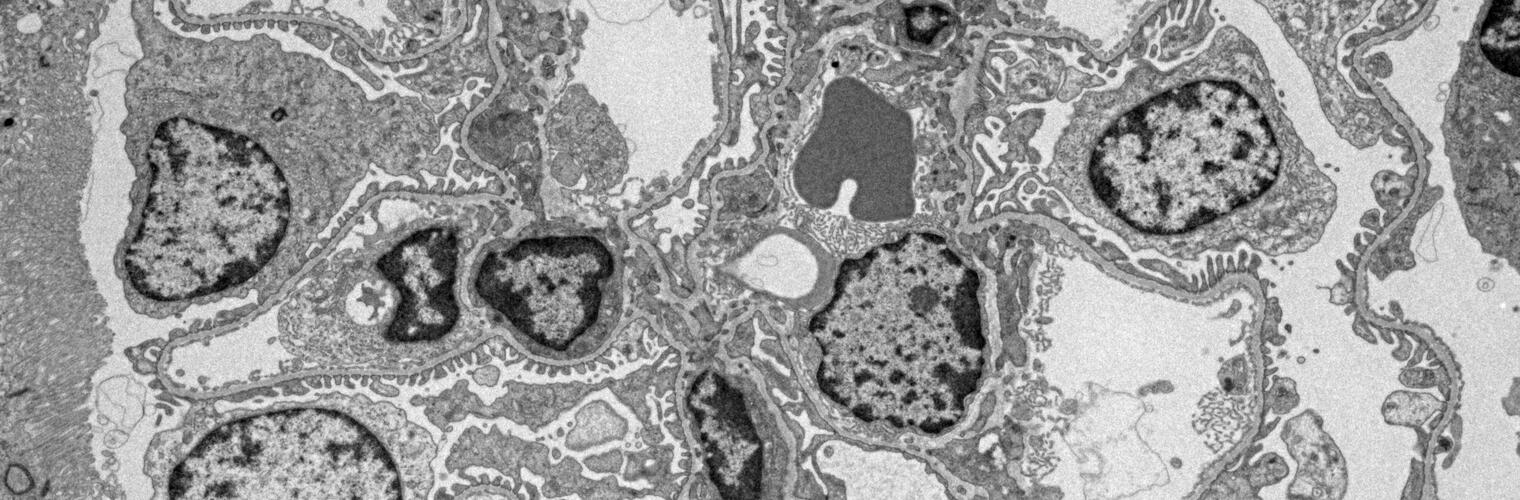

Macrophage infected with Legionella bacteria